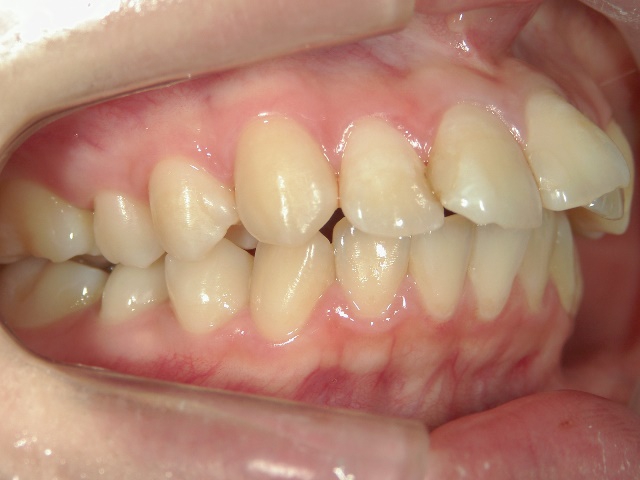

矯正歯科 治療前矯正歯科 治療前

矯正歯科 治療前

no.6_8296_治療前_右.jpgno.6_8296_治療前_正面.jpgno.6_8296_治療前_左.jpg